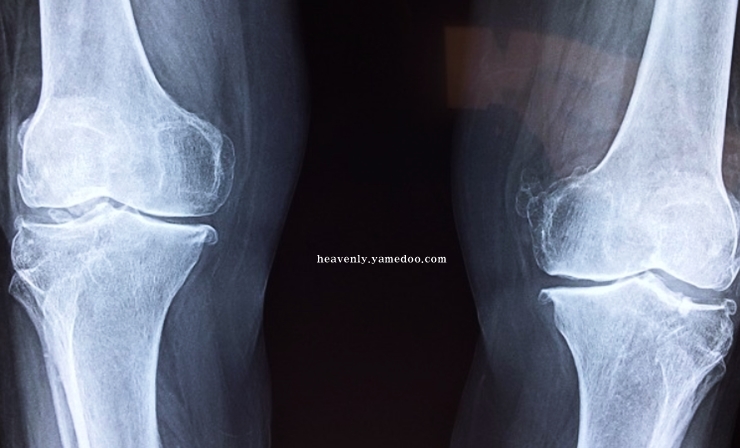

무릎 관절염은 초기에는 기본적으로 무릎을 움직일 때마다 정말 아픈 통증 증세가 나타납니다. 움직이지 않고 가만히 있는데도 저려오는 통증이 오고 잠시 통증이 진정되었다가 앉거나 일어설 때 또는 살짝 무릎을 굽힐 때 극심한 통증을 가져오는 것이 바로 관절염입니다.

관절염 통증은 증상이 악화될수록 움직일 때 물론 가만히 있을 때, 쉬고 있을 때, 잠을 잘 때도 나타납니다. 그래서 여러분의 무릎건강은 어떤지 자가진단 테스트를 해보겠습니다.